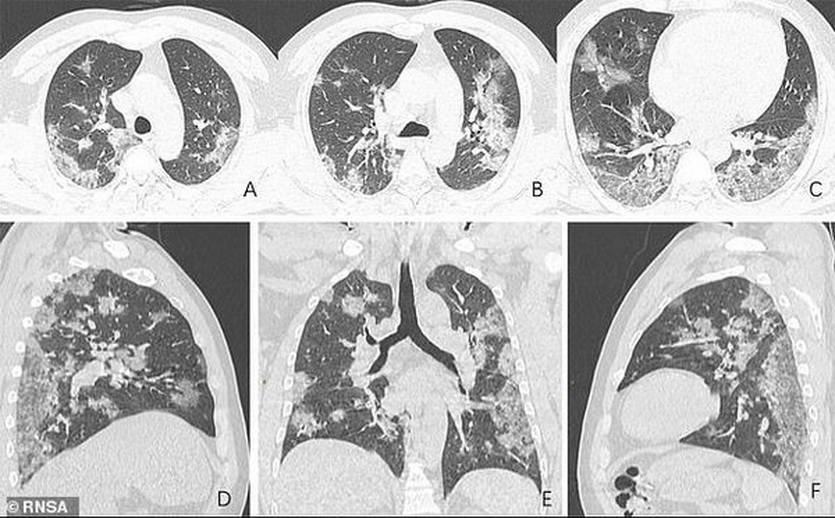

КТ

Компьютерная томография (КТ) создает подробные качественные изображения костей, кровеносных сосудов (при внутривенном контрастировании во время исследования), мягких тканей и органов. Исследование используют для диагностики онкологических заболеваний, травм, сосудистых патологий, поражения легких, брюшной полости и т.д.

КТ-аппарат выглядит как большой «бублик». Пациент лежит на столе, который постепенно движется, пока аппарат вращается вокруг и создает изображения поперечного сечения тела под разными углами. Затем изображения выводятся на экран компьютера, и с помощью цифровых алгоритмов создается трехмерное изображение.

Рентгеновские аппараты в некоторых случаях не могут диагностировать повреждения мышц, мягких тканей или других органов тела, что возможно с помощью компьютерной томографии. Кроме того, рентгеновские изображения представлены в 2D-формате, а изображения компьютерной томографии — в 3D.

COVID виден на томограмме даже не специалисту

Пресловутый COVID во многих случаях первично диагностируется уже на обычных рентгеновских снимках. То же с другими проблемами легких.

Даже на рентгеновских плоских снимках видно COVID